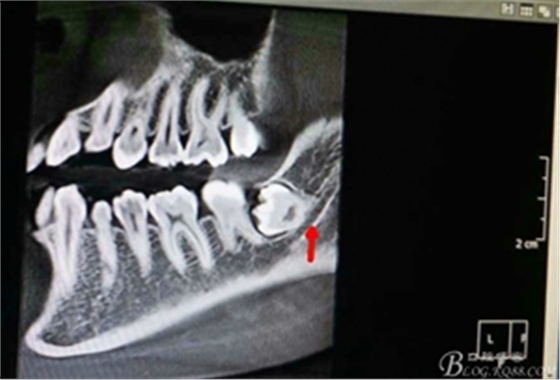

圖2.術(shù)前的cbct檢查:38牙冠周圍有骨組織覆蓋,下頜神經(jīng)管離38牙冠還有一定距離,在去除牙冠的時(shí)候,損傷神經(jīng) 的風(fēng)險(xiǎn)較小。38牙根舌側(cè)骨壁較薄。

圖4.術(shù)前的CBCT縱剖面檢查:38牙根1/3緊鄰下頜管,看紅色箭頭。提示盡量不要斷根,如根尖折斷,取根導(dǎo)致下頜神經(jīng)損傷的風(fēng)險(xiǎn)加大